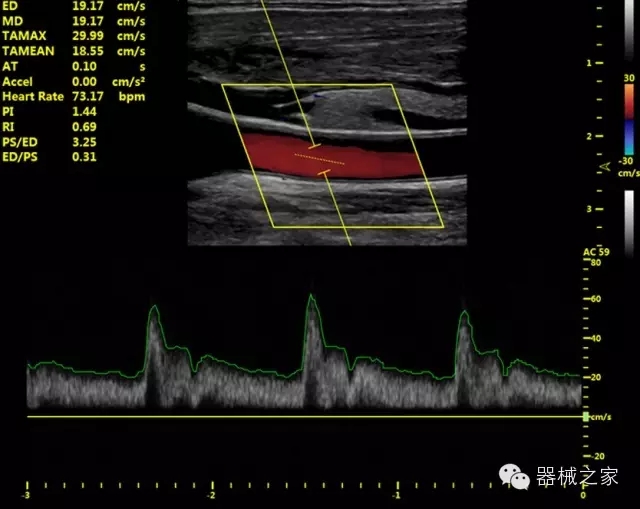

·獨(dú)有的HoloTM PW 實(shí)時(shí)3取樣門PW成像技術(shù),精確進(jìn)行血管診斷;

·一鍵優(yōu)化B、Color、PW,Auto Doppler自動(dòng)識(shí)別血管位置、偏轉(zhuǎn)角度等,提高工作效率;

·30°超廣角精細(xì)偏轉(zhuǎn)成像技術(shù),更優(yōu)異的頻譜圖像;

·IMT血管內(nèi)中膜自動(dòng)測(cè)量:為血管性疾病評(píng)估提供了有效的評(píng)估手段;